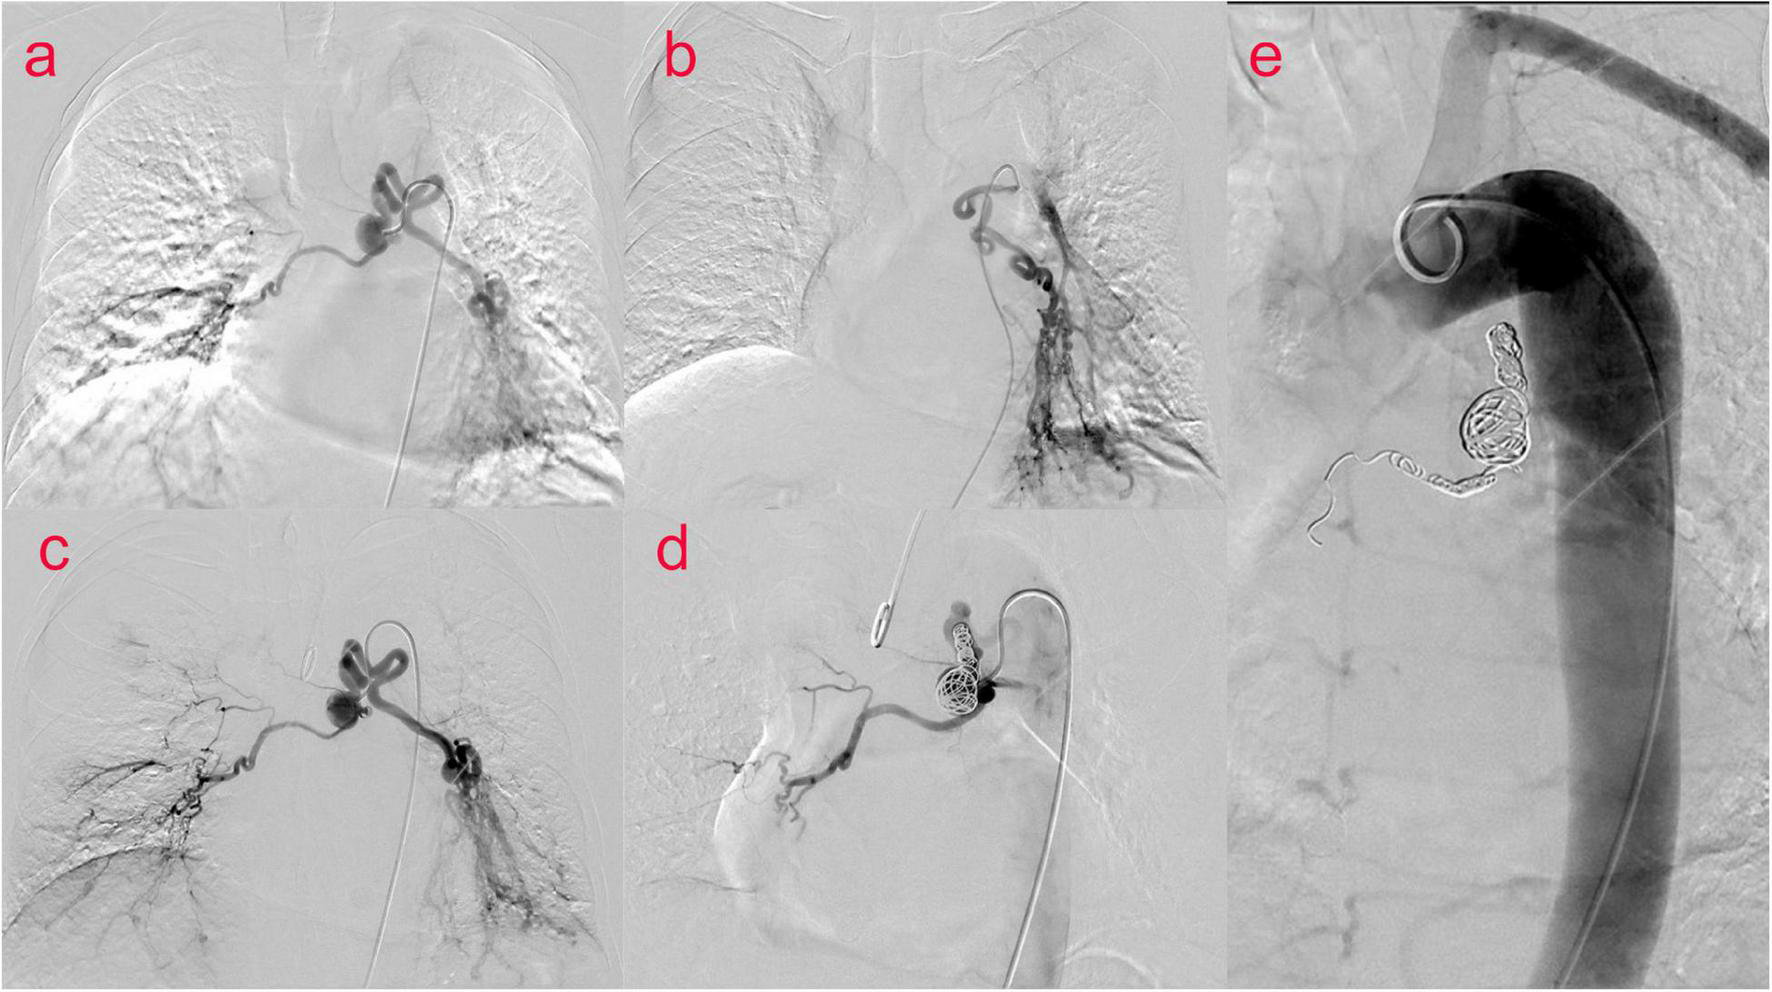

The patient was then taken to interventional radiology suite for angiographic evaluation. Percutaneous right femoral artery catheterization was performed under local anesthesia. With digital subtraction angiography(DSA), a 5F catheter was used for thoracic aorta and left and right bronchial artery angiography. Bronchial artery angiography showed no obvious abnormality in ascending, arched and descending aorta; It was equivalent to an aneurysm at the opening of the bronchial artery, approximately 1.5 cm × 1.7 cm. The left and right bronchial arteries were thickened, and disorder vessels were seen in the lungs, especially in the lower left lung, with pulmonary artery branches visible. Embolization of the left bronchial artery was performed with gelatin sponge particles (350–560 um), and the blood flow of the left bronchial artery slowed down significantly after embolization. We decided to embolize the BAA and prepare a thoracic aortic stent implantation. Before the procedures he signed a written informed consent to an endoluminal stent of the thoracic aorta in accordance with our institutional guidelines. Percutaneous right femoral artery puncture and catheterization under local anesthesia were performed, and 5F catheters were used for the thoracic aorta, abdominal aorta, left and right iliac arteries, and left and right bronchial arteriography with DSA. The distal end of the aneurysm was embolized with 700–900 μm microspheres and NESTER coils, and the tumor cavity was occluded. To achieve satisfactory angiographic results, no thoracic aortic stent implantation (Figure 2) was performed. The postoperative course was uneventful and the patient was discharged home on postoperative day 6. On CT scan at 4 months, we confirmed satisfactory placement of the aortic stent graft with exclusion and thrombosis of the BAA. No recurrence of bronchial artery aneurysm was found at 10 months after operation.

FIGURE 2

(Case one) Bronchial arteriography (a–c) showed an aneurysm at the opening of the bronchial artery of about 1⋅5 cm × 1⋅7 cm. Left and right bronchial artery thickening, disordered vessels in the lung, most obviously in the left lower lung, and pulmonary artery branches were seen. BAA and left bronchial artery and pulmonary artery fistula were considered. Percutaneous catheterization of the right femoral artery thoracic aorta, abdominal aorta, left and right iliac arteries, and left and right bronchial arteries was performed. During digital subtraction angiography (DSA) (d,e), the distal end of the aneurysm was embolized with 700–900 μm microspheres and NESTER coils, and the tumor cavity was occluded.